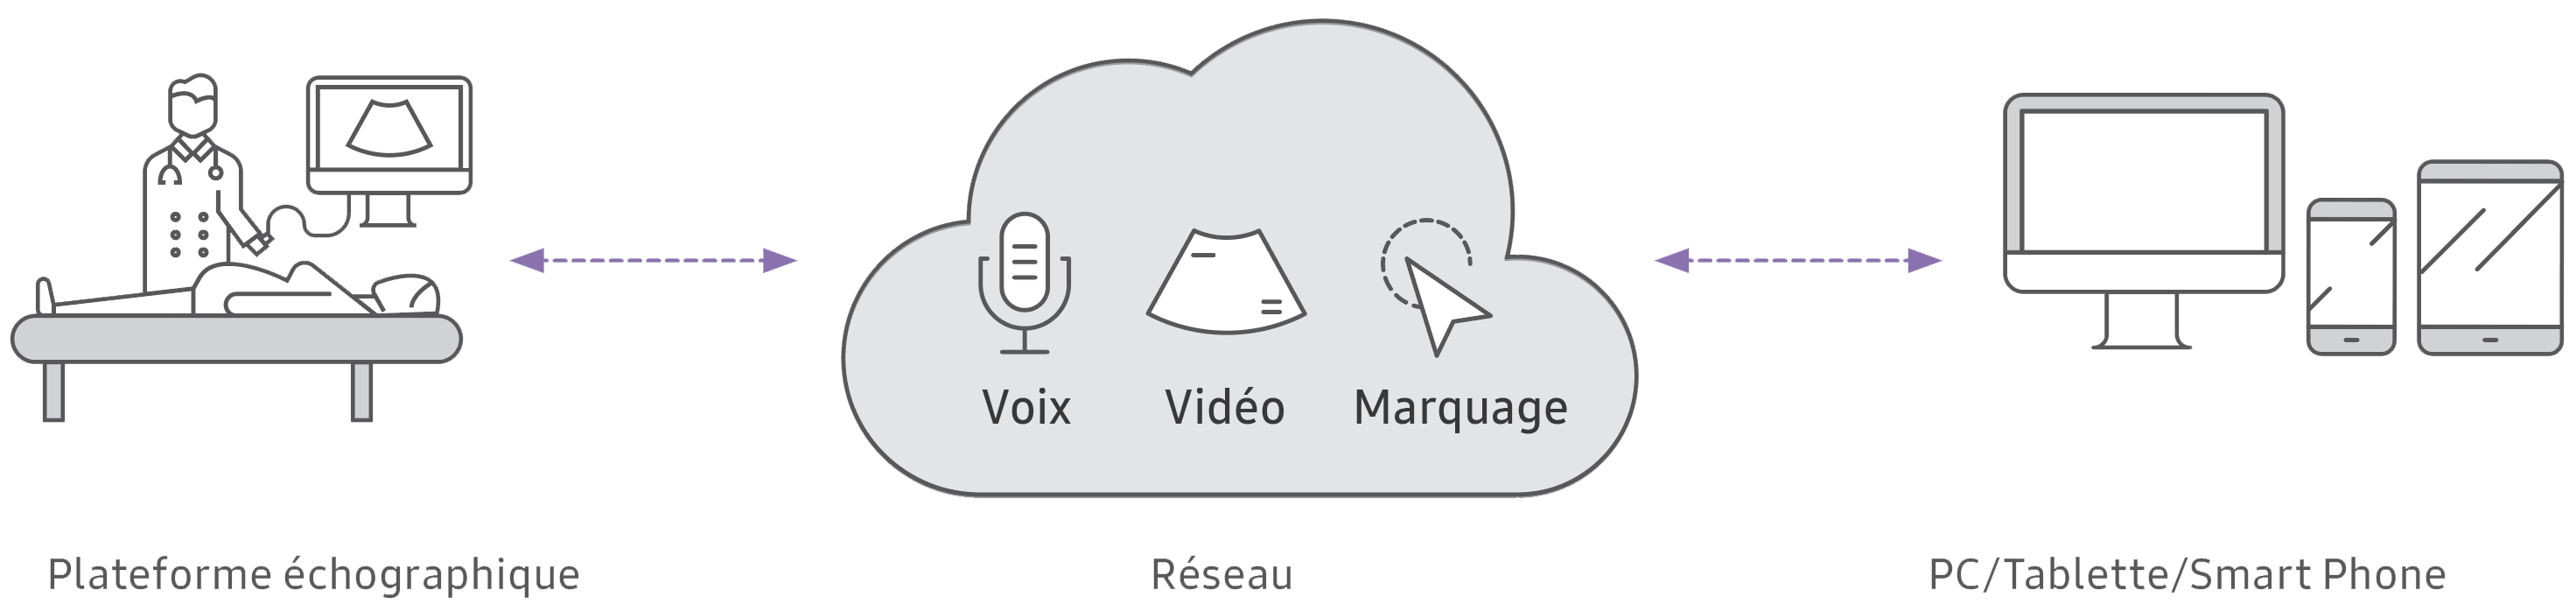

SonoSync™ est une solution de partage d’images échographiques à distance, sur tout type de support. Les fonctions chat audio, marquage en temps réel et affichage unique sur un seul écran (option MultiVue) favorisent une collaboration optimale et rapide entre plusieurs utilisateurs et développent la télé-expertise.

La synergie des solutions Samsung vous permet de partager en temps réel vos examens échographiques via la solution SonoSync™ et inviter les experts à visualiser vos examens à distance.

Depuis les écrans Samsung Flip, vos confrères pourront vous accompagner dans vos diagnostics et échanger sur des cas complexes via la fonctionnalité chat audio.

Grâce à ses options d’annotation, marquage et envoi instantané de fichiers médicaux, le Samsung Flip permettra de développer la collaboration entre professionnels de santé et améliorer la prise en charge des patients.